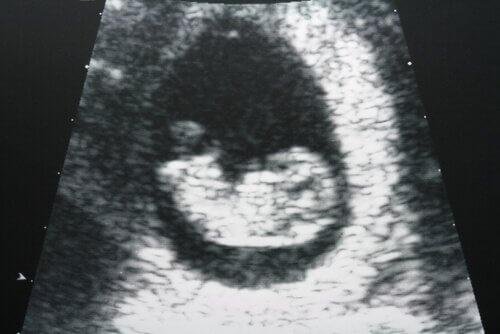

Ултразвукът е много чувствителен диагностичен тест, който може да открие потенциални промени в матката и яйчниците.